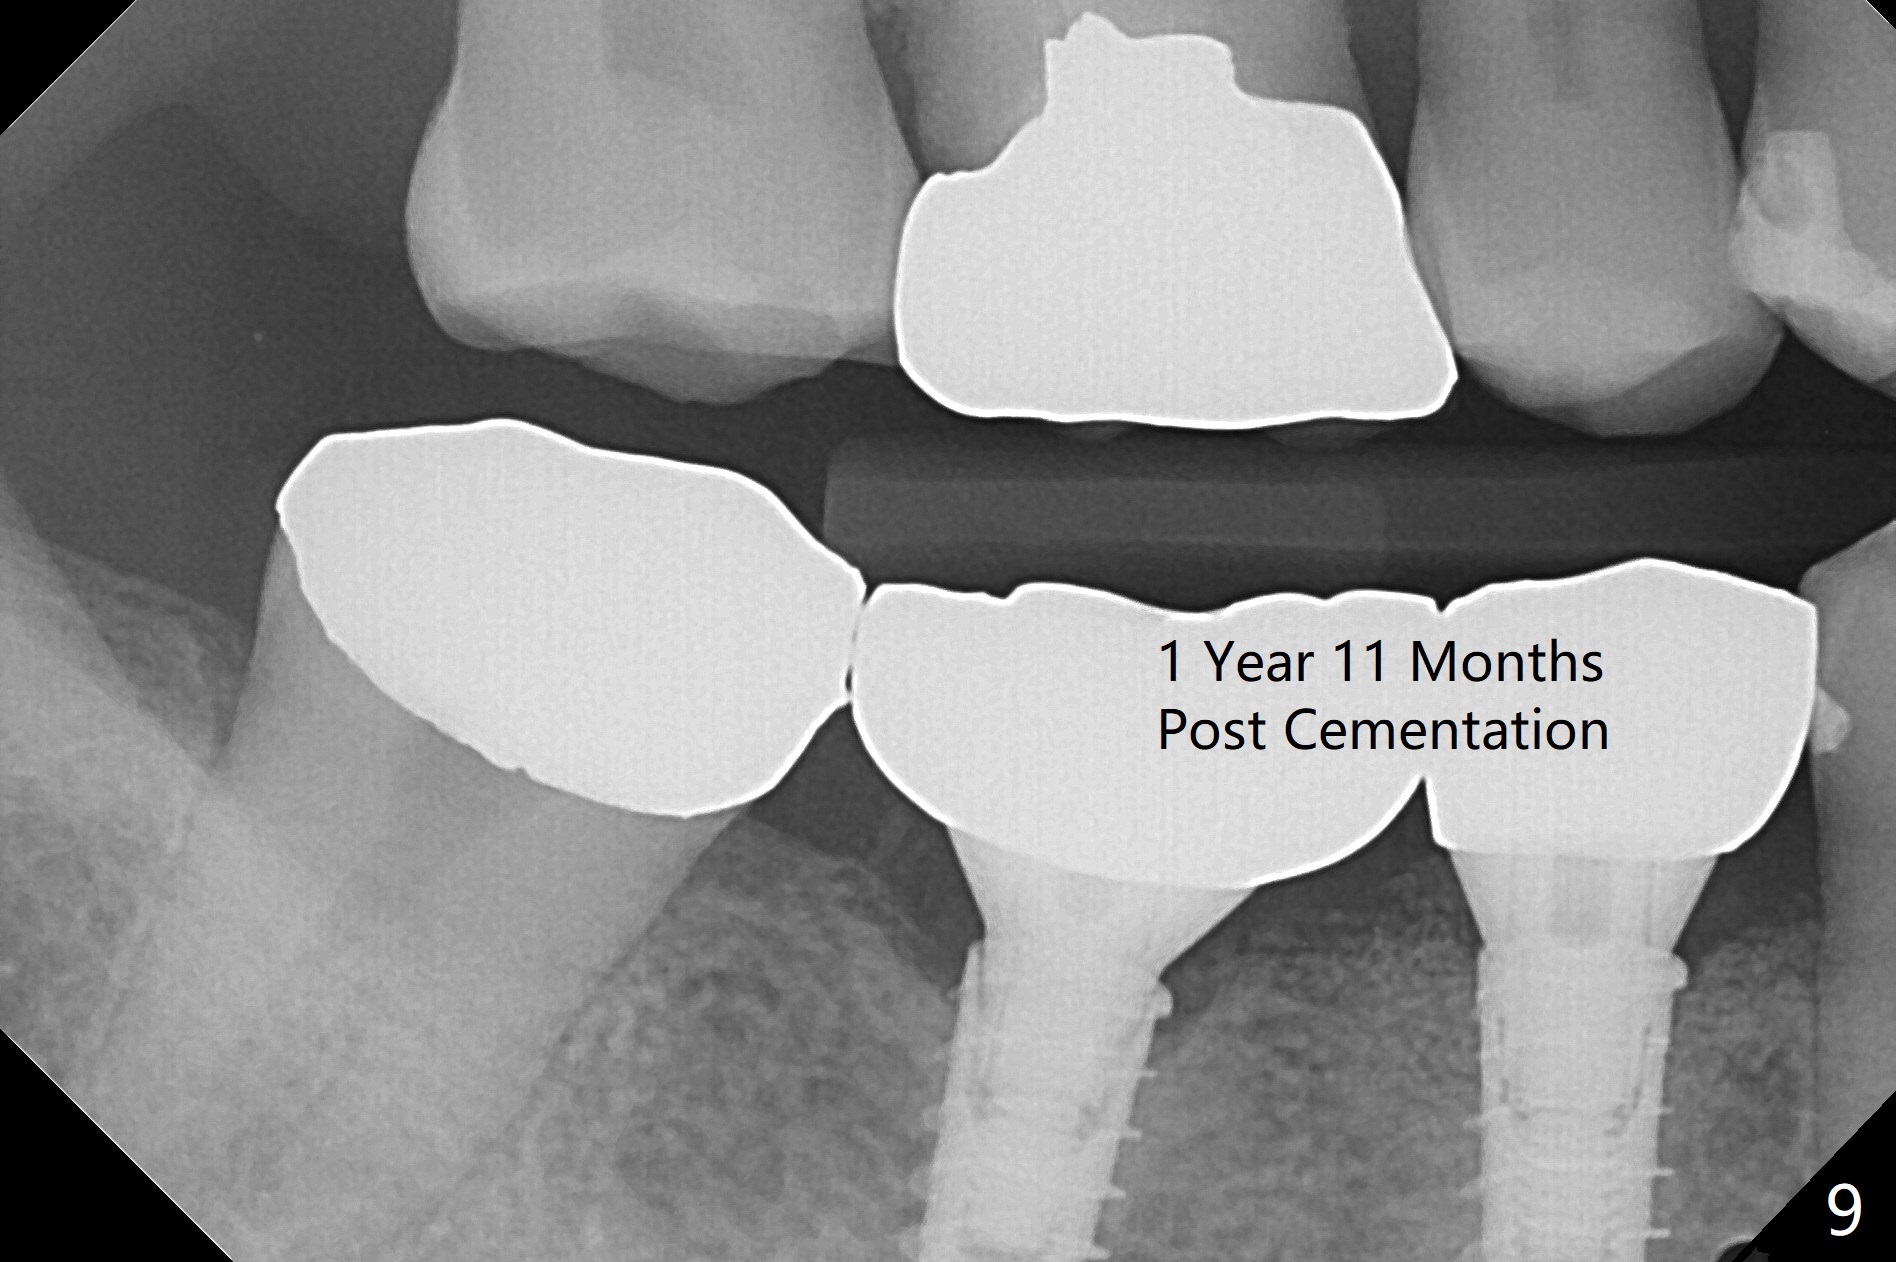

After incision, the ridge at #29 and 30 is found ~ 5 mm wide buccolingually. To place a 4x11 mm IBS implant at #30, the ridge is expanded using BEB technique (bone expansion and bending, Fig.1). It appears that the initial osteotomy at #29 is mesial (Fig.1 yellow dashed line: the distal surface of the root of the tooth #28). After moving the osteotomy distal, the final implant position at #29 (4x11 mm) is within normal limit (Fig.2). The bone at #29 seems to be not so dense that bending (using 1.6 mm drill) is not necessary (using Magic Split and Magic Expanders 3 and 3.8 mm). Later the implant at #30 (4x11 mm) is placed deeper (Fig.3). After placing bone graft around the implants/abutments and suturing, the ridge looks wider with apparent formation of the gingival bands around the abutments (Fig.4 *). Three months and a half postop, bone loss is minimal (Fig.5) and gingival bands forms around the abutments (Fig.6). Fig.7 is taken 1 month post cementation (panoramic X-ray). The patient chews normally 1 year (Fig.8) and nearly 2 years (Fig.9,10) post cementation. The crown at #31 needs recementation 2 years 7 months post #30 cementation; the incomplete seating of the abutment was noted for the first time (Fig.11). Five months later the patient is going to be retired and wants to travel abroad. After approval, the access hole was reopened; articulating paper shows under occlusion of the crown (Fig.12). Since the gap between the abutment and the implant is large, the abutment/crown complex seems to be necessary to be turned (Fig.13 curved arrow). The proximal surfaces of the crown need to be trimmed (straight lines). After turning, the crown sits down with screw tightening; the patient feels pain from the gingival cuff (Fig.14). After turning, the abutment appears to be completely seated (Fig.15). In fact the mesial and distal surfaces of the crown should have clearance from the neighboring teeth (Fig.14) so that pick-up impression is able to hold the crown/abutment complex securely (Fig.16: *). The crown is separated from the abutment after crown repair. They are seated together (loose connection) using the crown as a guide to seat the abutment. BW is taken without the crown. It appears that the abutment remains seated completely (Fig.17). The apical space is equal between #29 and 30 (Fig.17, as compared to Fig.5).